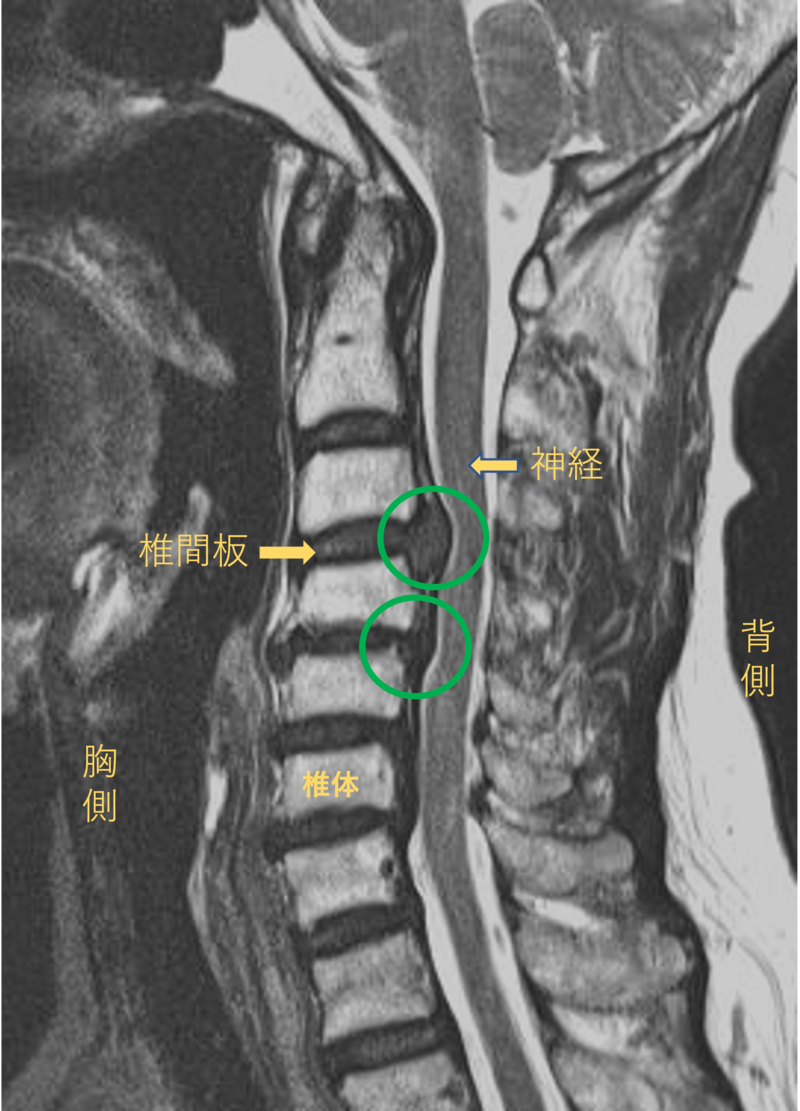

首を横から見たMRI画像です。

頚椎という骨と骨の間に椎間板と呼ばれるクッションがあります。

このクッションの中身が飛び出す状態が椎間板ヘルニアと呼ばれます。

このMRI画像では、椎間板が背中側に飛び出して神経が圧迫されることがしびれの原因となっておりました。